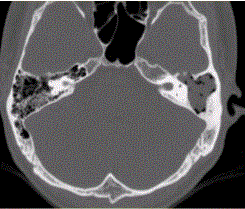

问题 患者男,25岁,右耳流脓液、听力下降5年。查体:右侧鼓膜穿孔,传导性耳聋,CT检查如下图。 慢性中耳炎引起颅内感染,累及部位多为

选项 A.额叶 B.顶叶 C.枕叶 D.颞叶 E.小脑半球 F.桥脑

答案 D